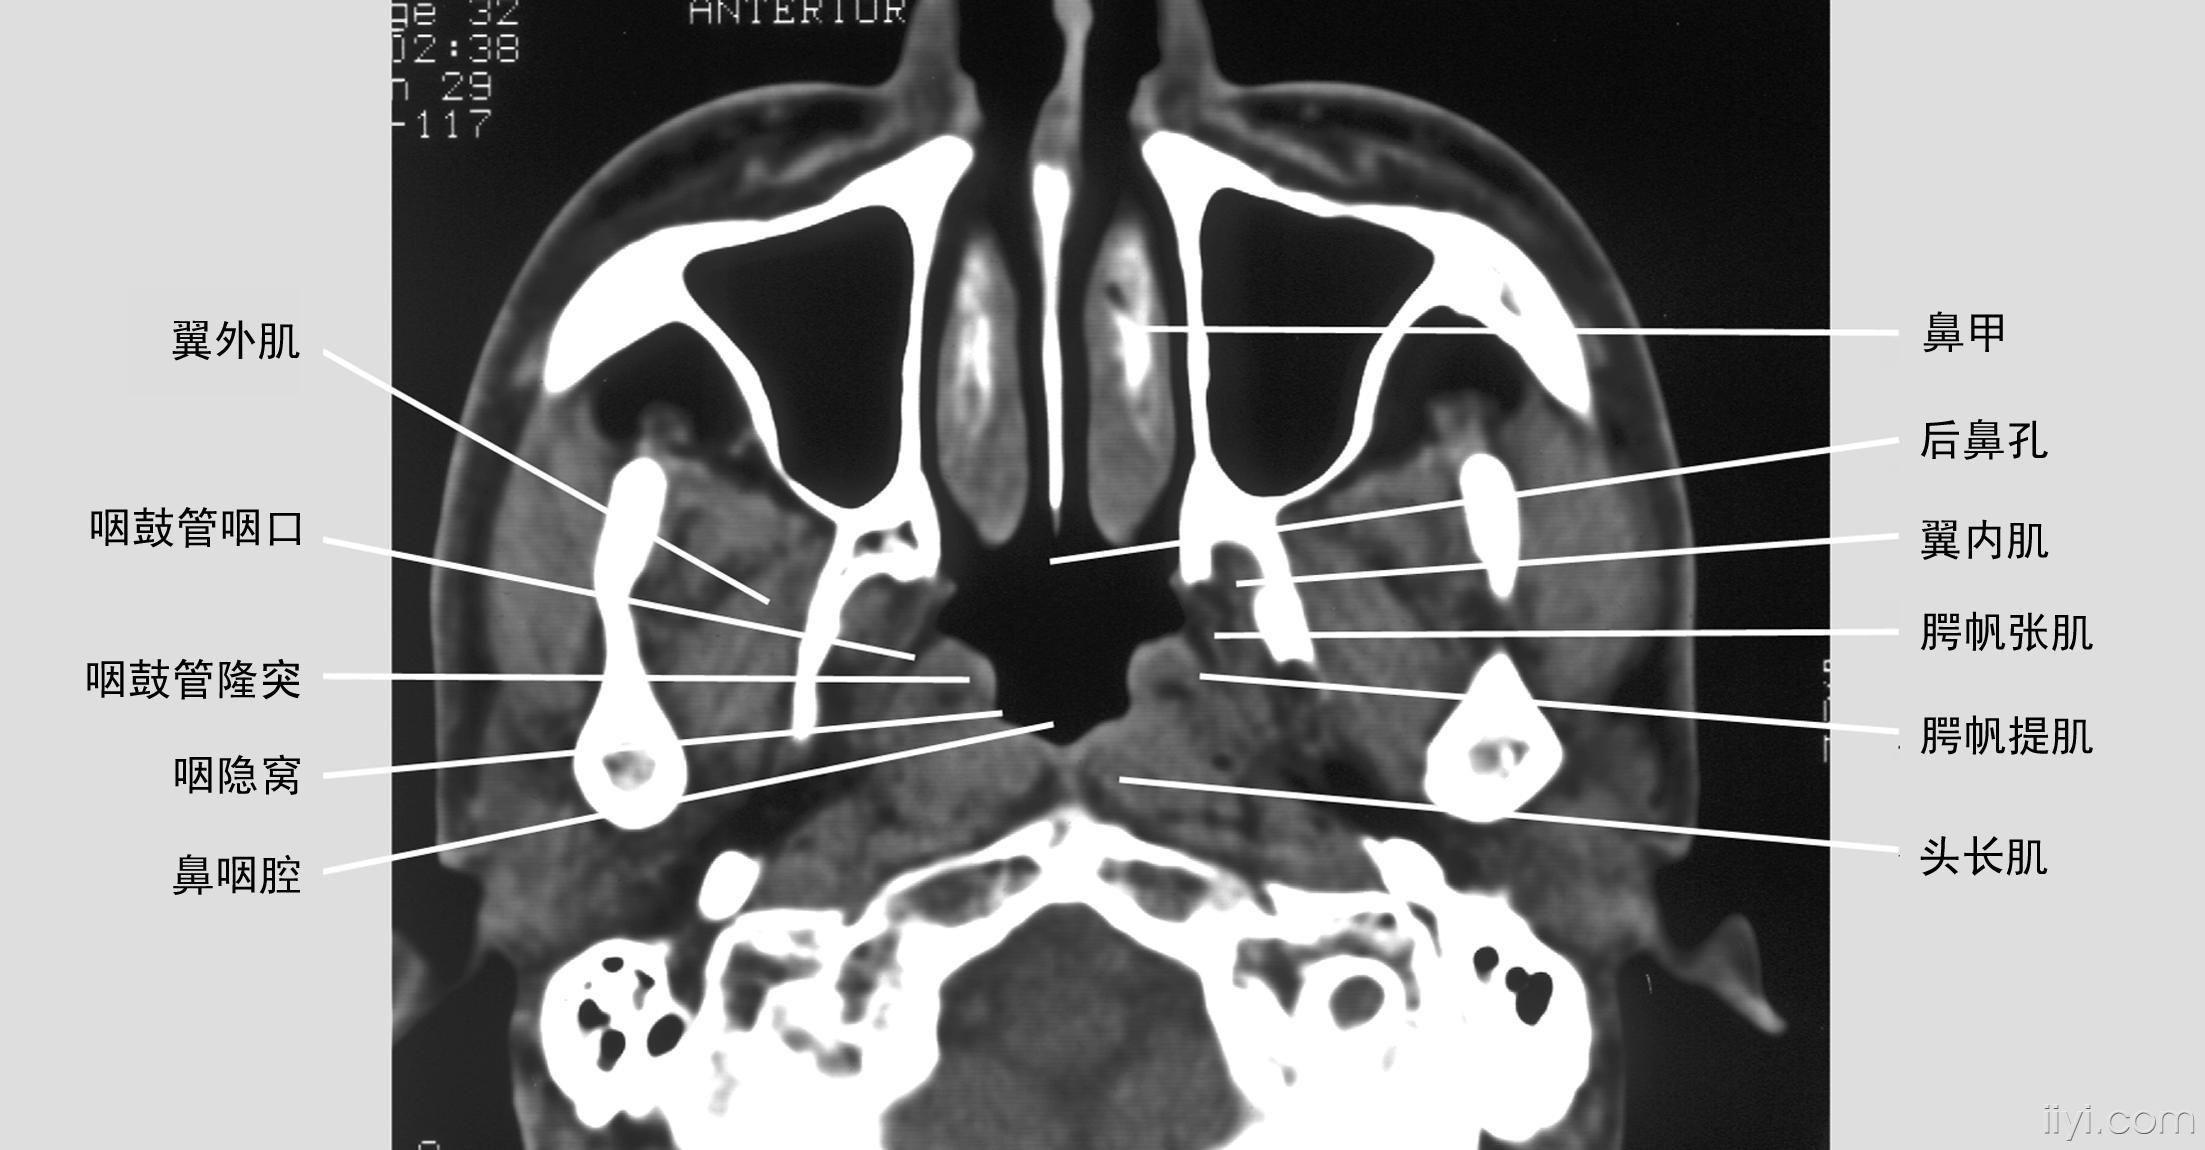

鼻咽癌的解剖图片

图片尺寸2205x1150